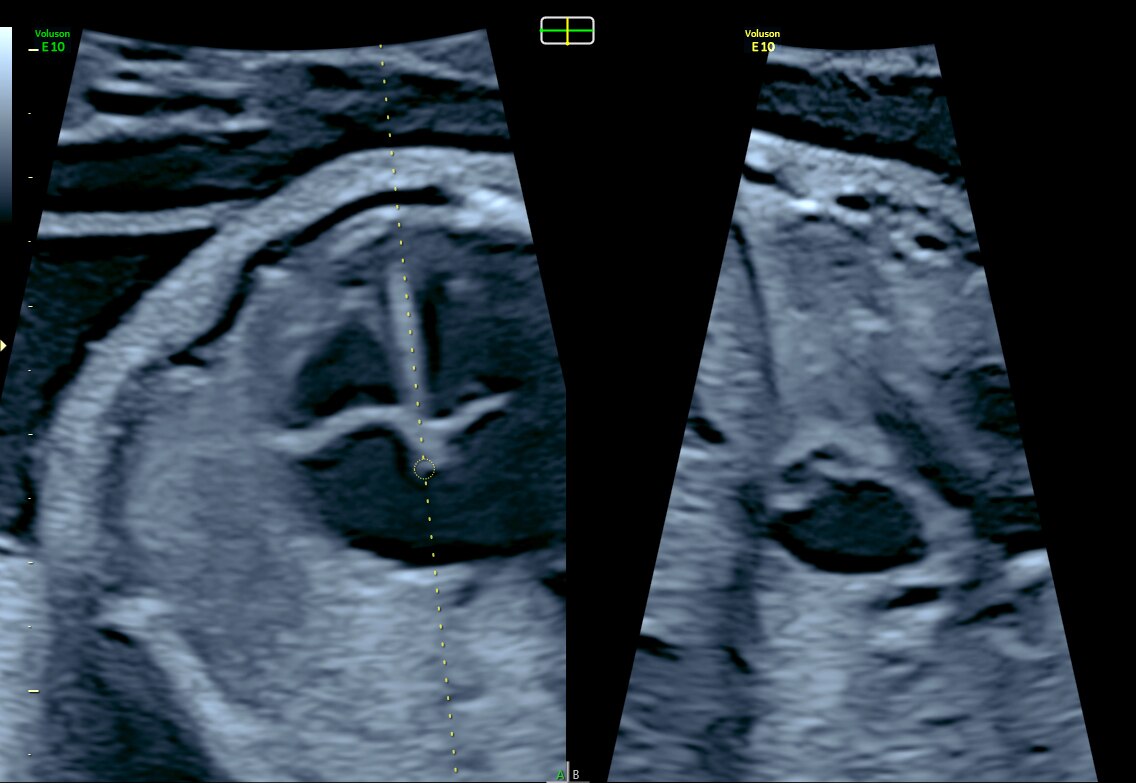

OmniView with multiple lines applied on 12-week fetus